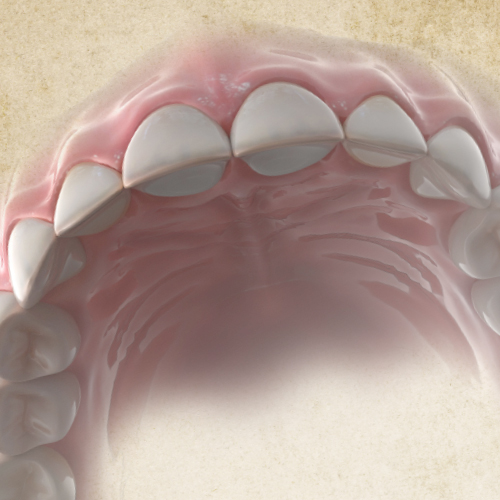

Dental Rehabilitation of the Atrophic Maxilla

Ankur Johri, DDS, MD, FACS

Friday, July 29, 2022

This Compendium eBook features a continuing education (CE) article presents important diagnostic and treatment planning principles of the All-on-4 treatment concept for the rehabilitation of the atrophic maxillary arch, and includes a case report illustrating free-hand implant placement using this treatment approach.